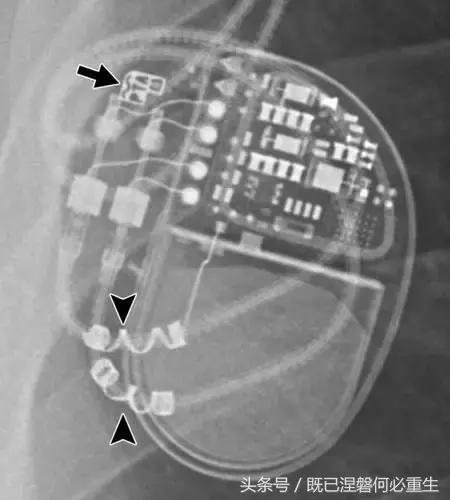

图 1A B 在75岁男性中植入式心律转复除颤器(ICD)的正常部件。

A,额叶胸片显示Medtronic(公司名字)单室ICD。 ICD的基本组件包括发生器,导线和围绕右心室(RV)导线的冲击线圈。 该系统还具有上腔静脉(SVC)中的冲击线圈,其可能不存在于所有系统中。 起搏器没有冲击线圈。 铅固定(见图8A)固定到胸部,并且可能或可能不在胸部X光片上可见。

B,引线通过头连接到发电机(黄色),其保持一个或多个连接端口。 所示系统需要三个端口(一个用于双极起搏或感测元件,一个用于RV休克线圈,一个用于SVC冲击线圈)。 正确放置的引脚将延伸超出连接器(见图9)。 制造商的标志和单个设备标识符的字体被反转,因为发电机被定向以允许在发生器口袋中适当的引线盘绕。 这种定位被设计成减少扭结的风险,这可能导致断裂。 有关制造商徽标的更多信息,请参见图4。